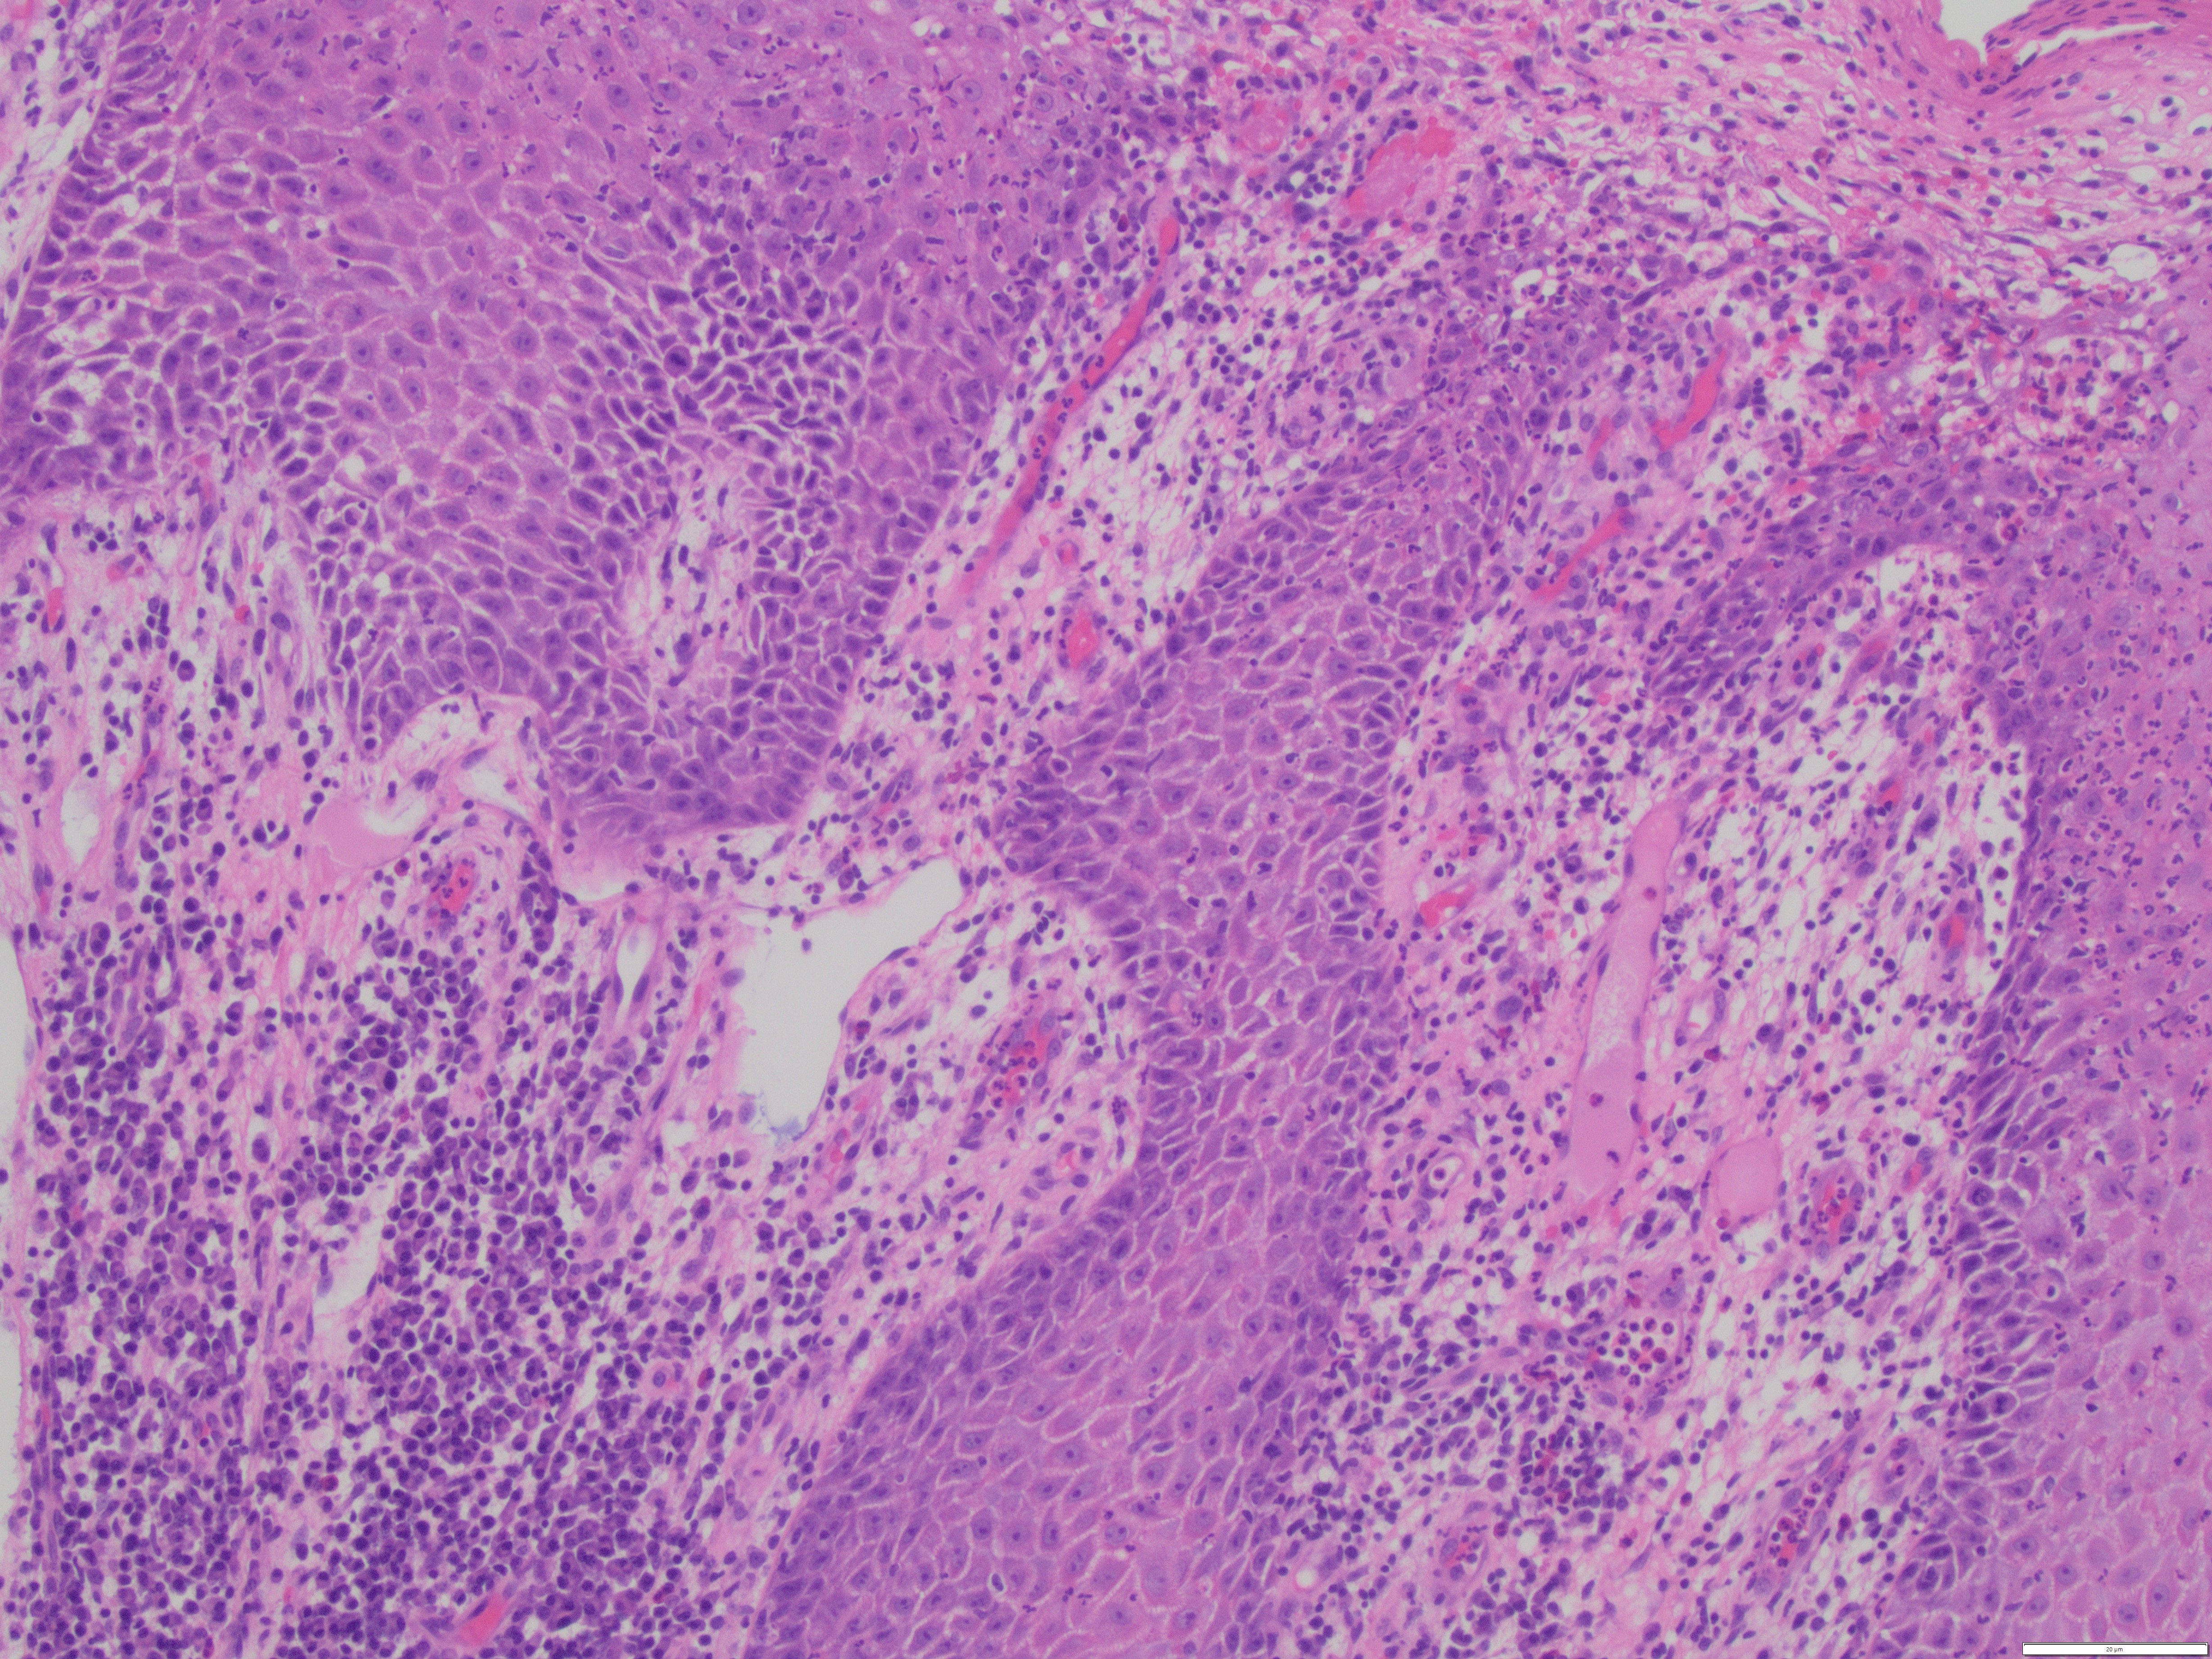

Discussion: Condyloma lata are cutaneous wart-like lesions of the genitalia caused by the spirochete T. pallidum (syphilis). Clinically, these lesions can resemble the more recognized counterpart, HPV-related condyloma acuminatum. However, on histologic examination, Condyloma lata contain epidermal hyperplasia with superficial neutrophils and intense dermal mononuclear cell infiltrate (classically dense plasmacytic inflammation as seen in this case). There is an absence of of the HPV-related koilocytic change, which are typically seen in a condyloma acuminatum.